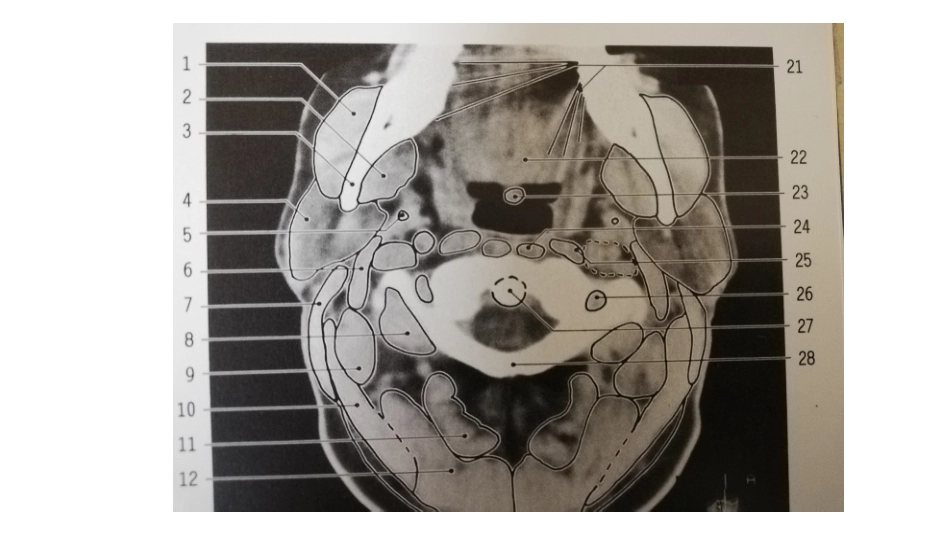

颈部正常轴位CT寰椎(悬雍垂)层面C2、C3层面(会厌上缘及以上)舌骨及会厌前间隙(C4)甲状软骨上切迹至声门声门下甲状腺中下部胸膜顶及稍下胸骨上切迹谢谢聆听

颈部正常轴位CT解剖图解